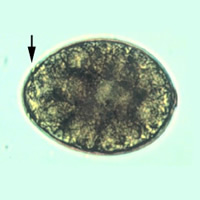

B: Eggs of Diphyllobothrium latum. These eggs are oval or ellipsoidal, with an

operculum at one end that can be inconspicuous. At the

opposite (abopercular) end is a small knob that can be barely

discernible. The eggs are passed in the stool unembryonated.

Size range: 58 to 76 µm by 40 to 51 µm.